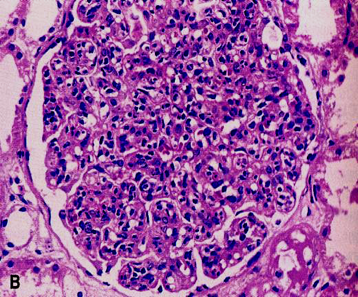

(1) 病理变化

肉眼观察: 肾脏肿大,充血、被膜紧张、表面光滑、色较红,故称大红肾。

光镜下: 弥漫性肾小球肿胀,细胞数目显著增多(hypercellular)是其主要特征。系膜细胞、内皮细胞明显增生肿胀为主,早期尚可见多少不等的中性白细胞和单核细胞浸润。增生的细胞使毛细血管管腔狭窄、甚至闭塞,从而导致肾小球缺血。少数严重病例可见肾小球壁层和脏层上皮细胞增生, 壁层细胞的增生形成新月体,易引起肾小球纤维化,如数量少,对功能影响不大。如病变广泛可发展为新月体性肾炎。

间质充血、水肿,少量淋巴细胞和中性白细胞浸润。肾小管上皮细胞可有水变性、脂肪变性及玻璃样变等。管腔内常含有各种管型,如透明管型、红细胞管型、白细胞管型等。